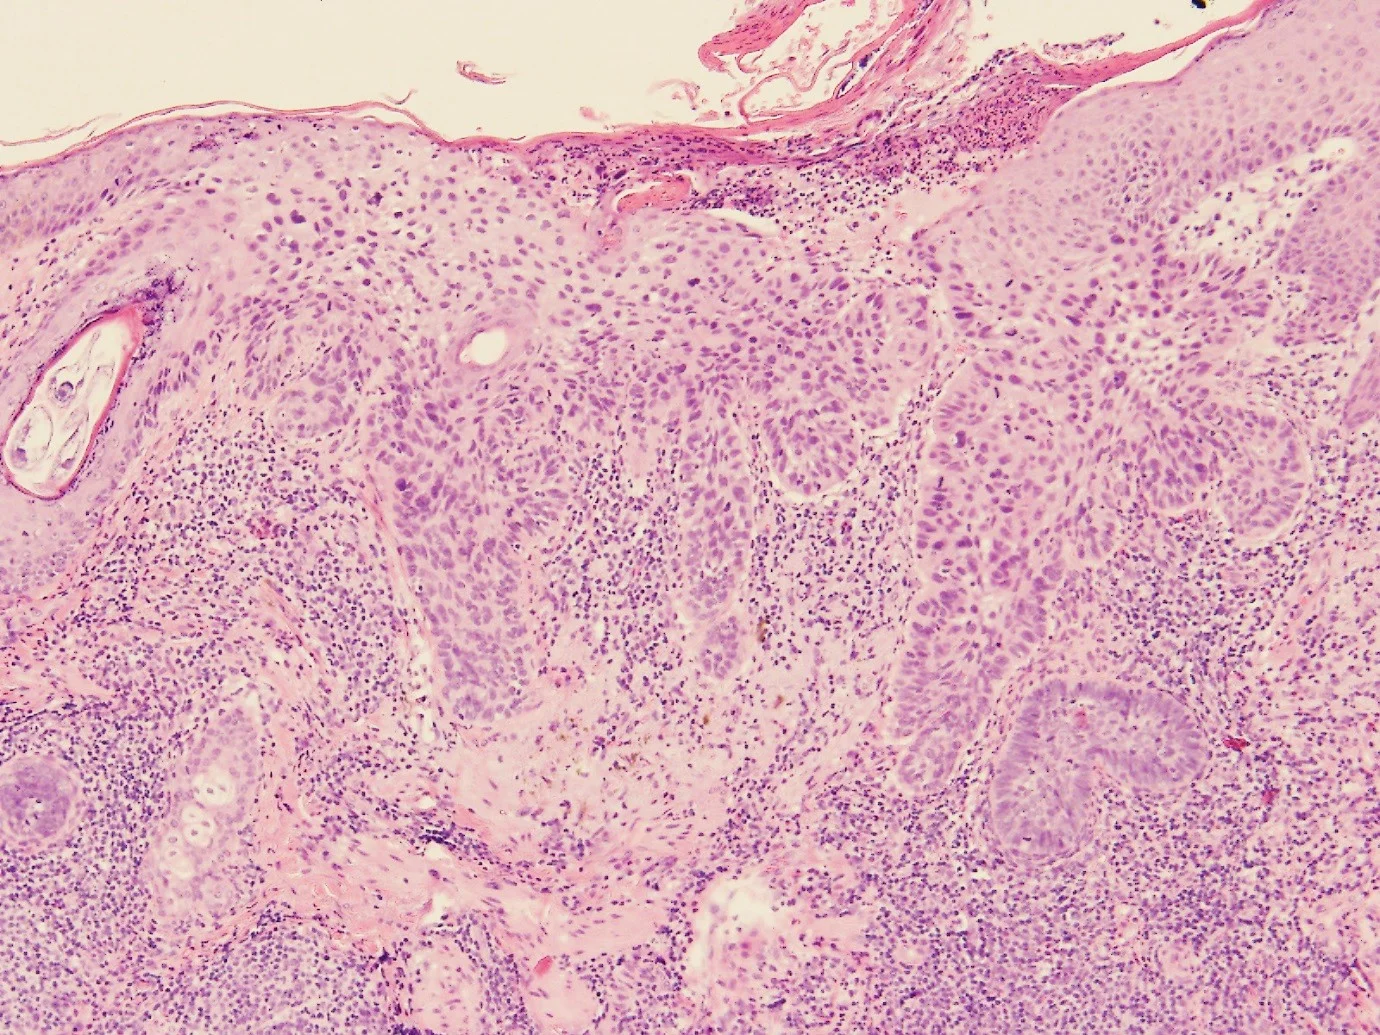

66year old male, presented with three hyperkeratotic scalp lesions, one of which is demonstrated below.